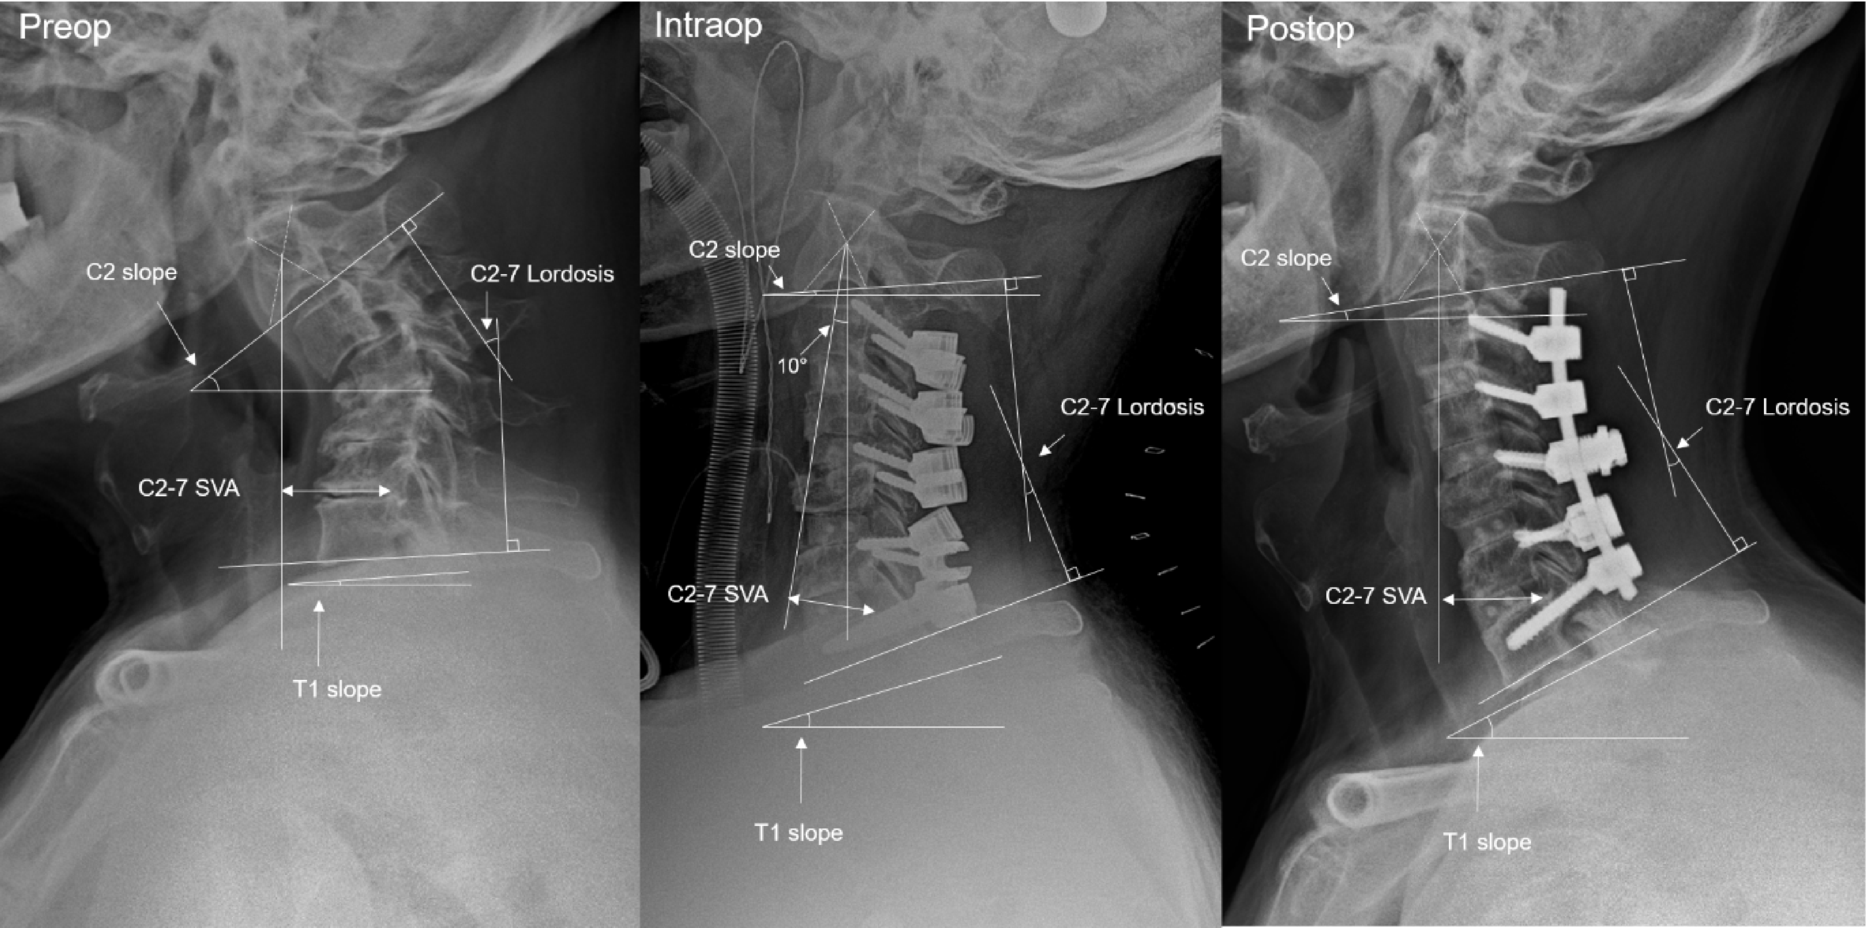

Fig. 2

From: Evaluating intraoperative C2 slope as a radiographic guide for cervical deformity correction

Radiographic measurements used in this study. The intraoperative film is taken with the patient in prone position with the table in 10° reverse Trendelenburg position. As a result, the axis is deviated by 10° causing 10° exaggerations of C2S and T1S.